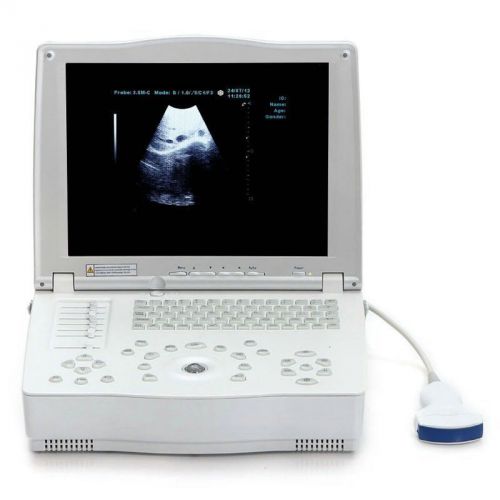

FULL DIGITAL LAPTOP ULTRASOUND SCANNER MACHINE + CONVEX PROBE CE 100% WARRANTY

Digital Ultrasound Scanner+Convex Transvaginal 2 probe/option linear probe+3D CE

Digital Ultrasound Scanner Ultrasonic Diagnostic + Multi_frequency Convex + 3D